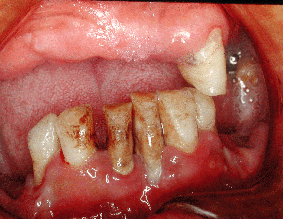

歯肉のメラニン色素沈着 スモーカーズ・メラノーシス 歯肉縁より5ミリほど根先の方に、暗赤色の帯状の着色が目立つ人が多くなって来ました。 メラニン色素沈着とされ喫煙に深い影響を受けており、喫煙者本人は当然ながら副流煙の影響も大きく、家族に喫煙者のいる家庭の子女・学童に、高率にメラニン色素の沈着が見られると報告されています。 |

| 写真1 30代女性 喫煙歴18年 | |